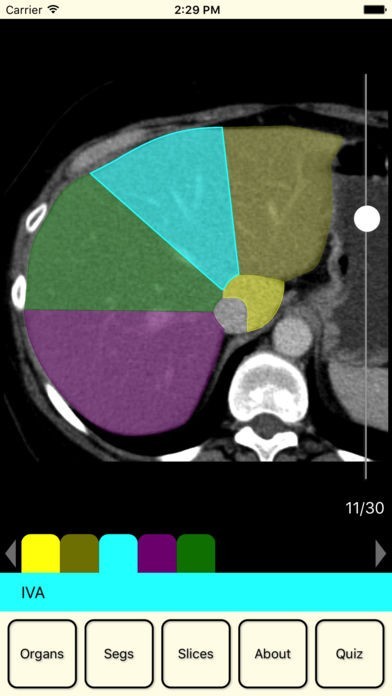

This application is a helper for students and doctors and can not be used to diagnose.

Content of this application has been provided by a certified specialist and practice radiologist Vitalii Rogalskyi.

Browse an organ image slice by slice to learn it segmental structure. Zoom this image for a good view. Test yourself in the quiz.